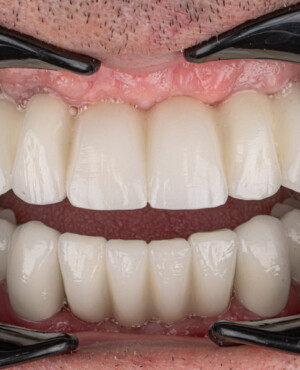

Prin realizarea coronițelor în conformitate cu parametrii exacți ai dinților protezați, această tehnologie asigură atât estetica, cât și funcționalitatea necesare, conferind un aspect natural întregii dentații.

- Aspect estetic natural și calitativ, care permite refacerea armonioasă a zâmbetului;

- Funcționalitate completă, asigurând procesul normal de masticație;